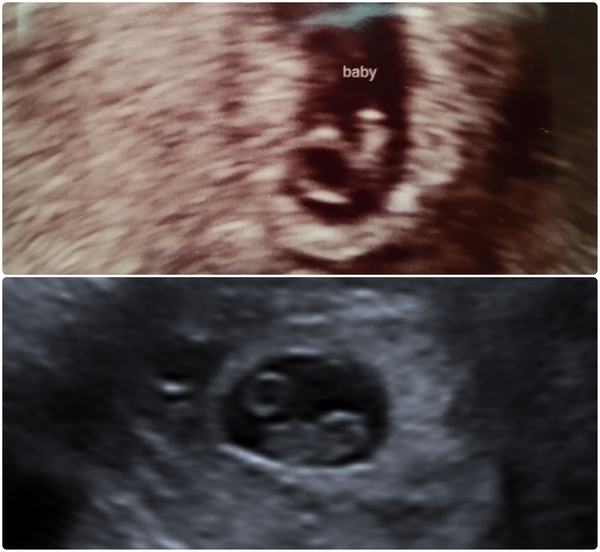

Trigger in pics...

Ladies can you help me please.. ( not for me but for a friend)

She found out a few weeks ago she was pregnant and went for a scan today.. this is what was found in her scan

They have referred her to the EPU Monday for another scan.. nothing much is being said but I wondered if you could help with any ideas as to if this is good news/ bad news or just too early?

Apparently she’s around 6 weeks but we reckon she could of ovulated later.

Thank you 🙂